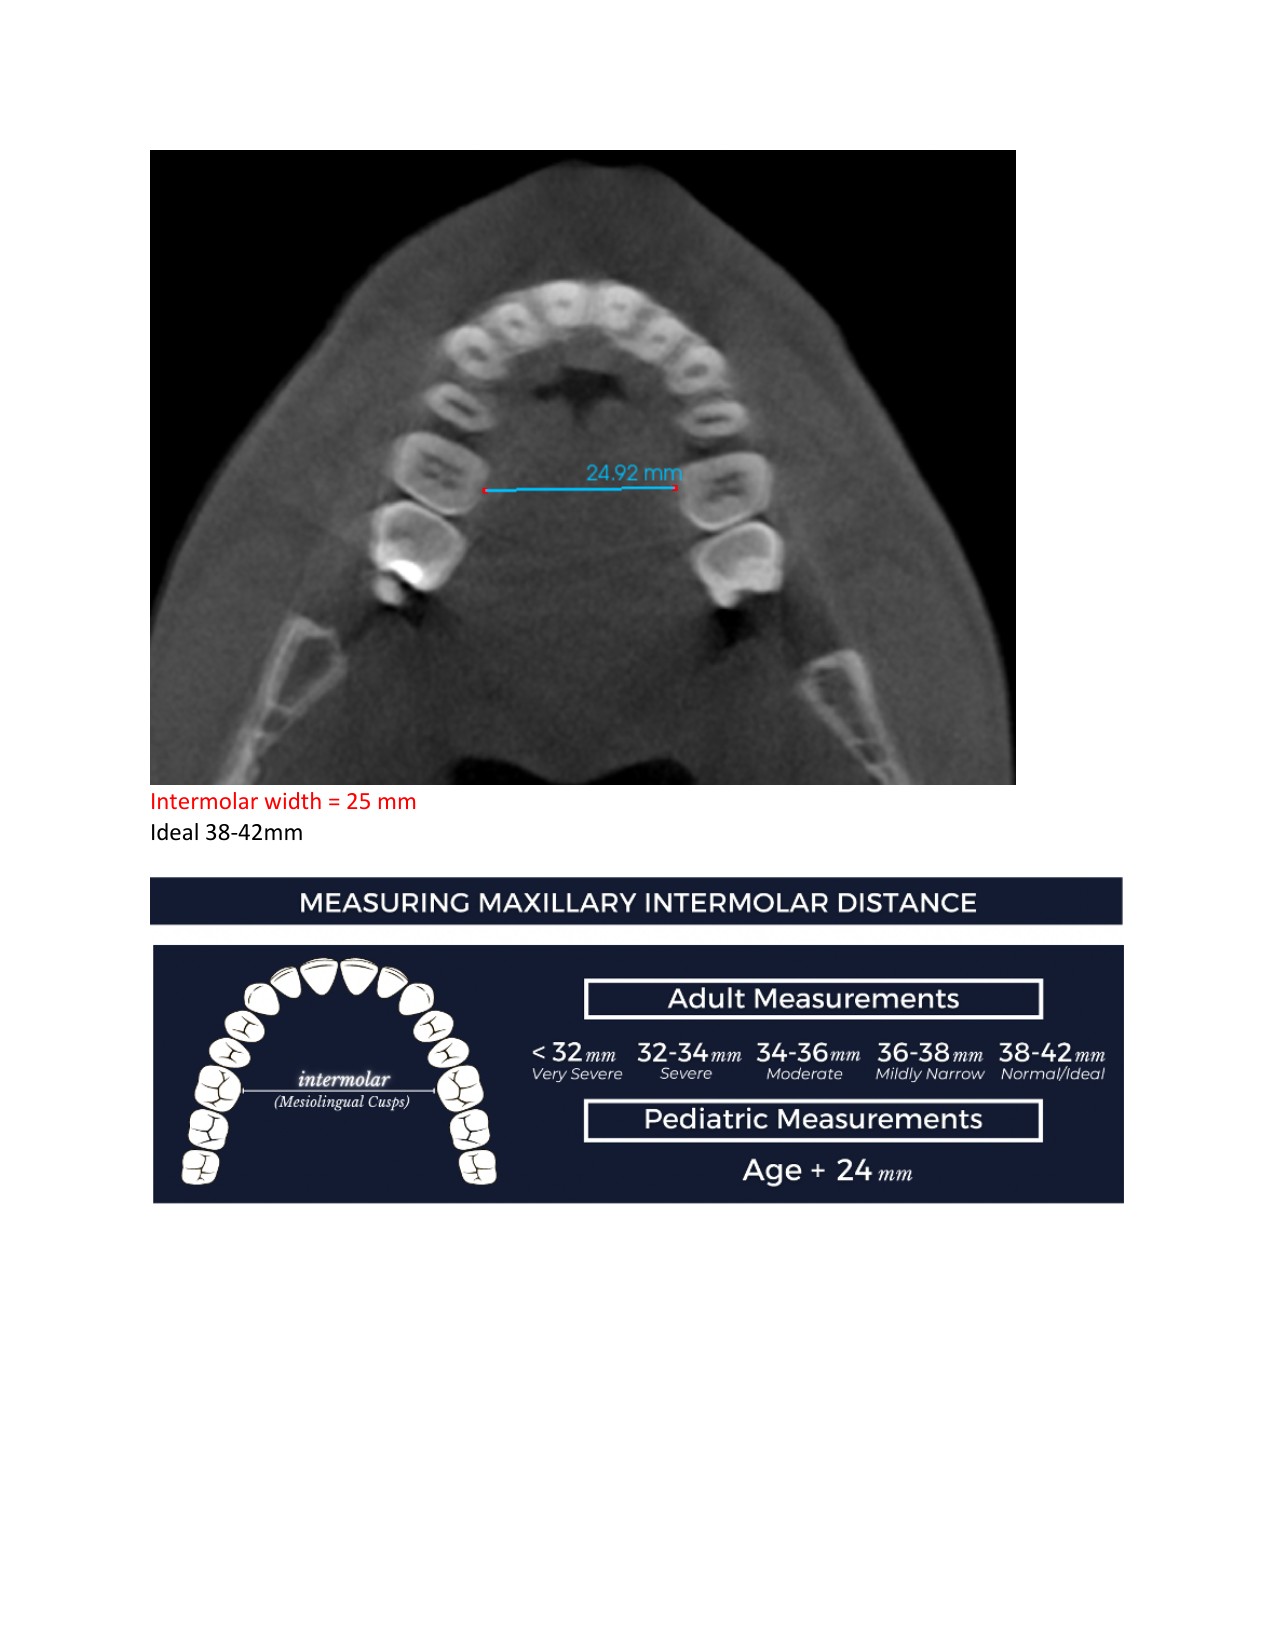

My jaws are severely underdeveloped (bimaxillary hypoplasia), my face is crooked due to a tilted upper jawbone (maxillary cant), and I have a posterior crossbite on both sides, which worsens my bite and facial imbalance. My palate is so narrow and high that my tongue is pushed backward and downward, making it hard to swallow and speak. It disrupts the whole balance of my body, and every time I swallow, my body has to compensate, which creates tension in my neck, jaw, and shoulders and affects my posture. I constantly have ear pressure and pain in my jaw joints, and together with my exhaustion, it’s almost unbearable.

To get the help I need, I now have to seek care in the US, where I can have advanced jaw surgery. This includes a DOME procedure, where the upper jaw is widened by separating the bone in the midline and lifting the narrow palate to create space for the tongue and improve the airway. I will also need double jaw surgery to correct the position of my jaws and restore balance to my face and body. These procedures are not without risks, but without them, I don’t have a life. I am surviving, but I am not living. I’ve already saved and borrowed as much as I can, but it’s not enough. That’s why I’m asking for your help. If you can contribute to my surgery, I would be deeply grateful, no matter the amount. The money will go toward the remaining surgical costs, essential preparations, aftercare, braces, and travel expenses. I would also be thankful if you would consider sharing my story with others who might be able to help.